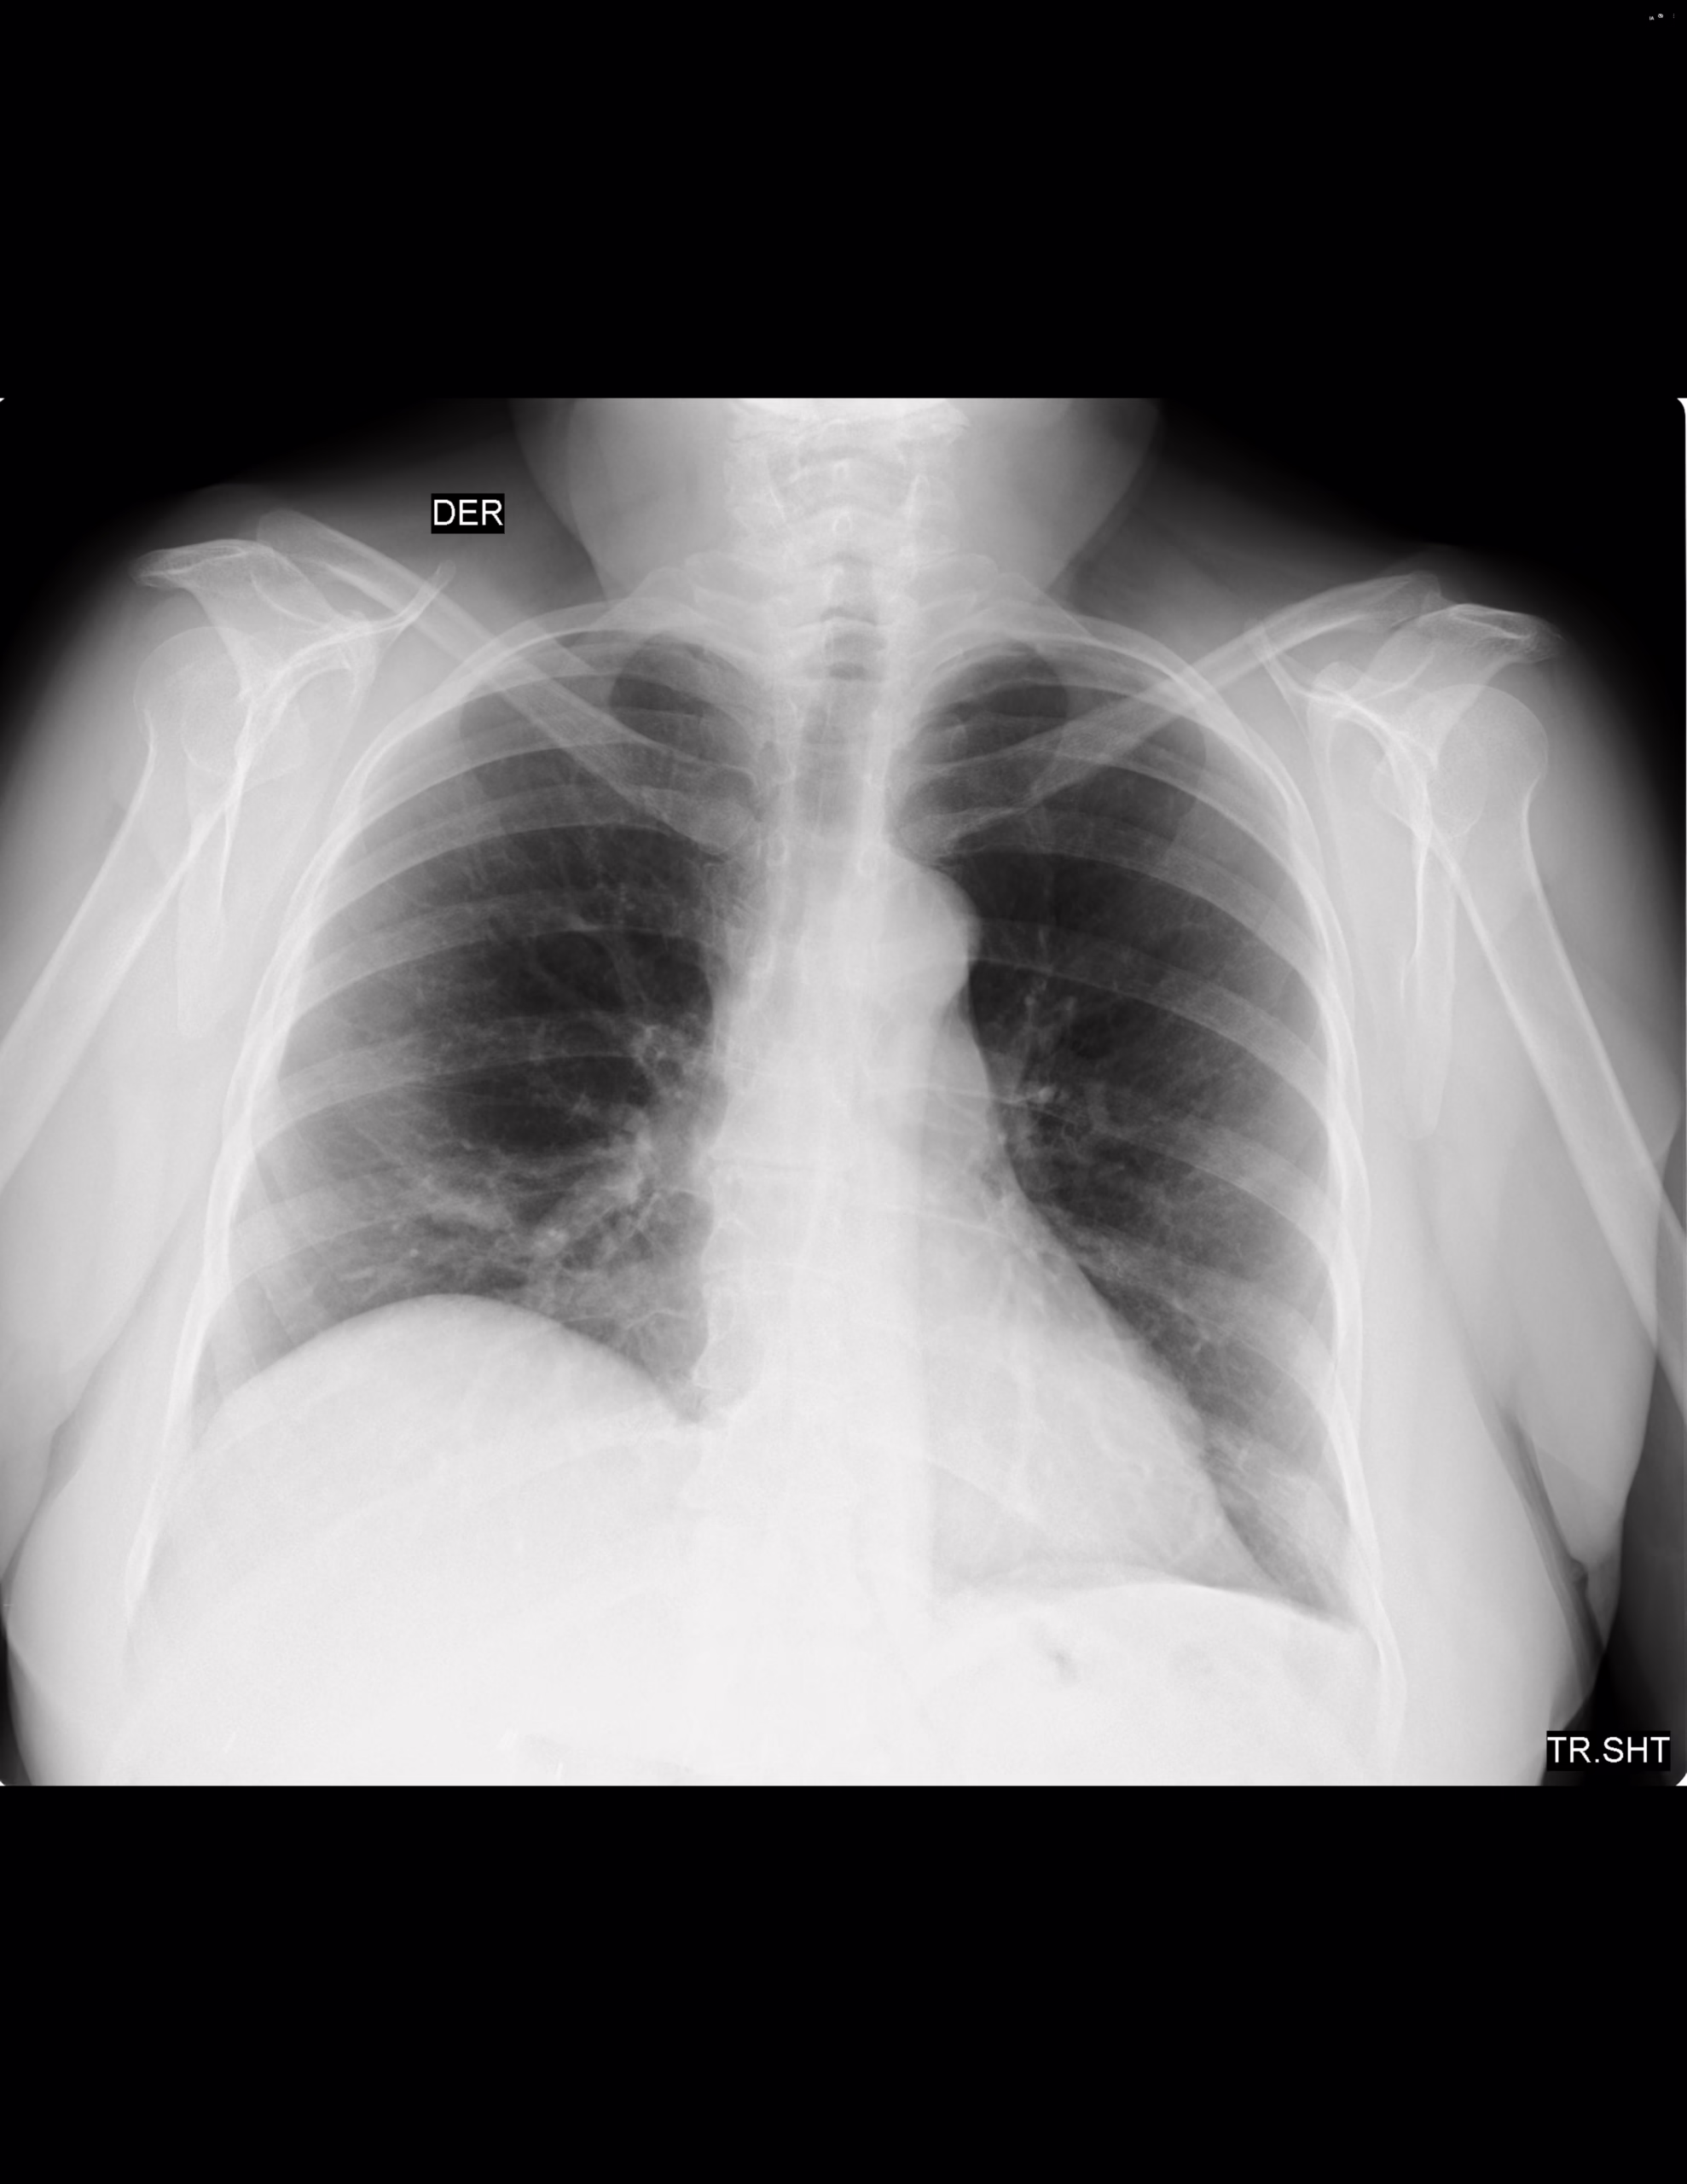

PA Y LATERAL DE TORAX

LA PROYECCION RADIOLOGICA OBTENIDA NOS MUESTRA LOS SIGUIENTES HALLAZGOS:

-Tejidos blandos, con densidad conservada, simétricos, sin evidencia de alteraciones.

-Estructuras óseas, sin evidencia de lesiones líticas, blásticas o perdida de la contigüidad. Existen osteofitos marginales.

-Vía aérea permeable, tráquea central.

-Mediastino, central, sin evidencia de alteraciones. Botón aórtico con escasas calcificaciones.

-Corazón, central, con índice cardiotorácico menor a 0.5.

-Hilios pulmonares, sin alteraciones.

-Trama bronco-vascular, con adecuado trayecto y calibre.

-Campos pulmonares, con adecuada densidad, sin evidencia de opacificaciones, nódulos, masas o derrame pleural

-Recesos costofrénicos y cardiofrénicos se observan libres.

-Espacio retroesternal con pérdida de su amplitud.

-Llama la atención la elevación del hemidiafragma derecho con diferencia de 5.6 cm.

OPINIÓN RADIOLÓGICA:

EN EL PRESENTE ESTUDIO RADIOGRÁFICO, SIN EVIDENCIA DE LESIONES PARENQUIMATOSAS.

EXISTE ELEVACIÓN DEL HEMIDIAFRAGMA DERECHO CON DIFERENCIA 5.6 CM, DE ORIGEN A DETERMINAR.

LA PÉRDIDA DEL ESPACIO RETROESTERNAL PODRÍA CORRESPONDER A AUMENTO DEL TAMAÑO DEL VENTRÍCULO DERECHO VS ORIGEN A DETERMINAR.

ATEROESCLEROSIS Y CAMBIOS OSTEODEGENERATIVOS.

LEER DESCRIPCIÓN Y OTORGAR VALOR DIAGNÓSTICO.

CORRELACIONAR CON DATOS E HISTORIA CLINICA DEL PACIENTE